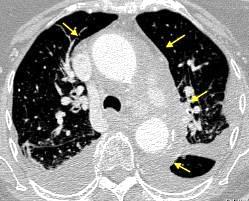

Ganglios retroperitoneales (flechas negras)

germinales del testículo izquierdo Nódulos pulmonares múltiples. (flechas verdes). Ganglios paratraqueales. (flechas amarillas). Dudoso ensanchamiento retrocrural (flechas negras)

Panda A et al. “Straddling Across Boundaries”. Thoracoabdominal Lesions: Spectrum and Pattern Approach. Curr Probl Diagn Radiol, 2015